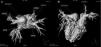

Para elucidação diagnóstica foi realizada RMC em aparelho Philips Achieva® 1,5T, no qual foi obtida sequência de cine (Balance Steady‐State Free Precession [b‐SSFP]) e phase contrast para disfunção valvar. Como no momento da realização do exame a paciente estava no terceiro mês de gestação, optou‐se pela não utilização de contraste, não sendo possível a realização de angiorressonância de veias pulmonares. Através da cine‐ressonância, foi verificada a presença de duas veias pulmonares direitas com óstios adjacentes e aparentando desembocar em AD, enquanto as duas veias pulmonares esquerdas desembocavam normalmente em seu sítio no AE. Não foram observadas comunicações interatriais ou interventriculares e havia aumento de cavidades direitas, VD hipertrófico e seio venoso coronariano dilatado. Aventou‐se a suspeita diagnóstica de DVPA parcial para explicar os achados da RMC e a hipótese de veia cava superior esquerda persistente levantada à ecocardiografia foi confirmada. Neste momento, institui‐se tratamento clínico com diuréticos e dada continuidade à gestação. Oito meses após o parto a paciente realizou nova RMC, desta vez complementada com angiorressonância de veias pulmonares (Figura 1), que confirmou o diagnóstico de DVPA parcial. O exame também verificou redução de diâmetros e volumes direitos quando comparados à RMC anterior, o que pode ser explicado pelo estado hipervolêmico induzido pela gestação da paciente naquela ocasião.

Assim, a associação de métodos de imagem não invasivos é útil para a confirmação ou exclusão do diagnóstico de DVPA parcial. Nesse sentido, a RMC, ao aliar técnicas de angiografia com alta capacidade de resolução espacial e caracterização tecidual, é reconhecidamente importante6–8. Sem fazer uso de radiação ionizante, esse método permite delinear a anatomia dos grandes vasos com ampla avaliação do retorno venoso pulmonar e quantificação do volume de shunt esquerdo‐direito. Além disso, a RMC, através da análise da anatomia e morfologia das câmaras cardíacas e da função ventricular, é primorosa na mensuração do volume e fluxo no VD, também medindo massa ventricular, espessura e função contrátil. Desse modo, em pacientes com suspeita de DVPA parcial, a RMC fornece extensa avaliação superando grande parte das limitações da ecocardiografia e pode ser considerada como alternativa não invasiva à realização de cateterismo cardíaco para melhor indicação terapêutica, incluindo diferentes estratégias cirúrgicas6–9. No caso relatado, devido à condição gestacional da paciente quando da realização do exame de RMC, a DAPV parcial teve que ser constatada somente através da sequência em cine (Figura 3). A angioressonância com gadolínio, a fim de demonstrar a anormalidade da vasculatura de forma tridimensional, foi executada em um segundo exame (Figura 1).

VCI: veia cava inferior; VPID: veia pulmonar inferior direita; VPIE: veia pulmonar inferior esquerda; VPSD: veia pulmonar superior direita; VPSE: veia pulmonar superior esquerda.